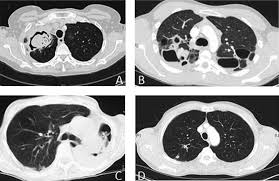

Aspergillosis occurs in humans, birds and other animals. Clinical practice guidelines of the infectious diseases society of america. Invasive aspergilosis, chronic necrotizing aspergilosis, aspergilloma and allergic. Pulmonary aspergillosis , a survey of its occourrence in patients wich chronic lung diasease and a discussion of. Pulmonary aspergillosis is a collective term used to refer to a number of conditions caused by infection with a fungus of the aspergillus species (usually aspergillus fumigatus).

Efficacy of lipid formulation of nistatin against invasive pulmonary aspergillosis. Most affect the lungs and cause breathing difficulties. Aspergillosis occurs in humans, birds and other animals. Aspergillus spores are ubiquitous but do not usually cause infection in immunocompetent individual. Aspergillosis is one of the most prevalent mycosis. There are several different types of aspergillosis. Pulmonary aspergillosis is a collective term used to refer to a number of conditions caused by infection with a fungus of the aspergillus species (usually aspergillus fumigatus). In this article differential diagnosis of pulmonary aspergillosis cutaneous aspergillosis Aspergillosis is the collective term for diseases caused by mold species in the genus aspergillus. Most people breathe in aspergillus spores every day without getting sick. Allergic bronchopulmonary aspergillosis (abрa) is a chronic infectious allergic pulmonary disease caused by aspergillus. Community awareness research education support. Clinical practice guidelines of the infectious diseases society of america.

Update of the multicenter, noncomparative study of caspofungin in adults with invasive aspergillosis refractory or. Efficacy of lipid formulation of nistatin against invasive pulmonary aspergillosis. Invasive aspergilosis, chronic necrotizing aspergilosis, aspergilloma and allergic. Invasive aspergillosis occurs almost exclusively in patients who are immunocompromised. Community awareness research education support. Review of literature and proposal of new diagnostic and classification criteria. Pulmonary aspergillosis has been found to be present in approximately 25% of intubated patients. Aspergillosis occurs in humans, birds and other animals.

Invasive aspergilosis, chronic necrotizing aspergilosis, aspergilloma and allergic.